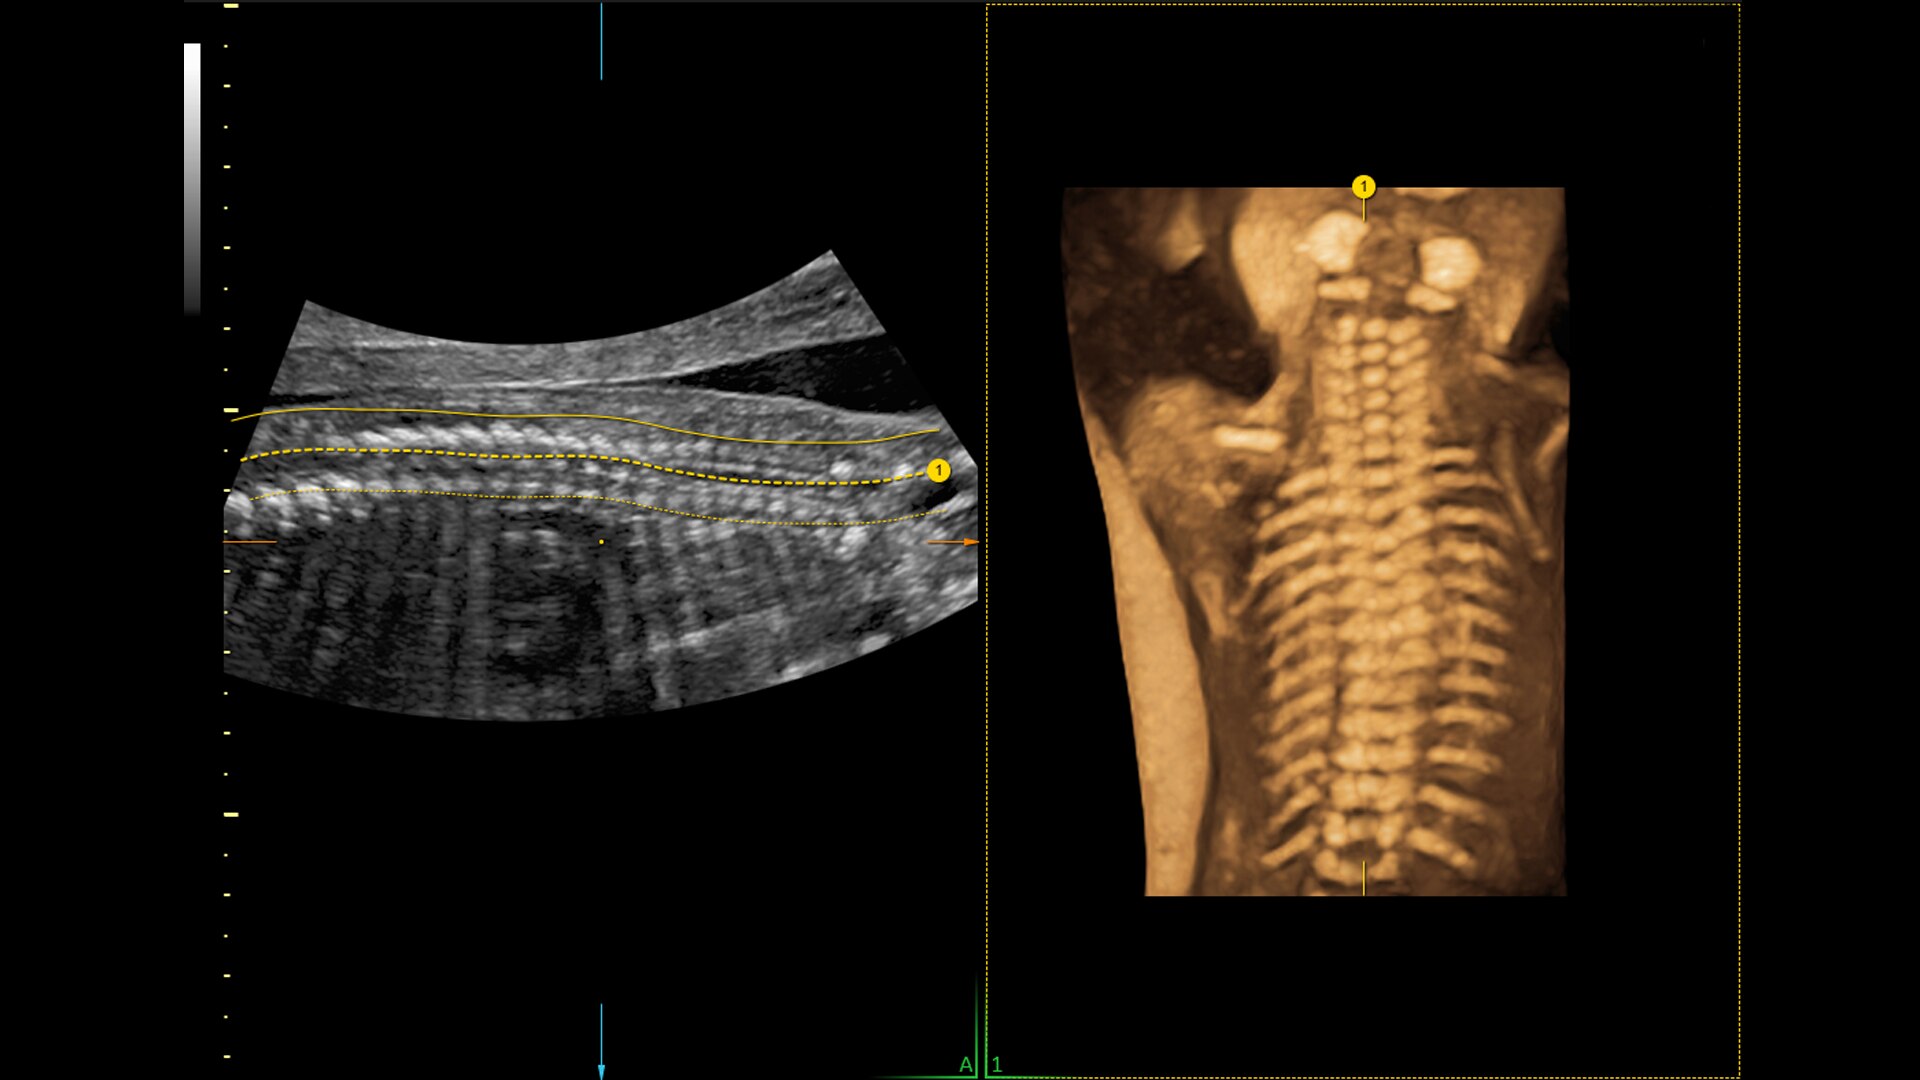

Spine Trace

Welcome to easy 3D in 1/2 the time. Simply trace the spine and the system automatically acquires the volume and displays the coronal view - with 83% less keystrokes.